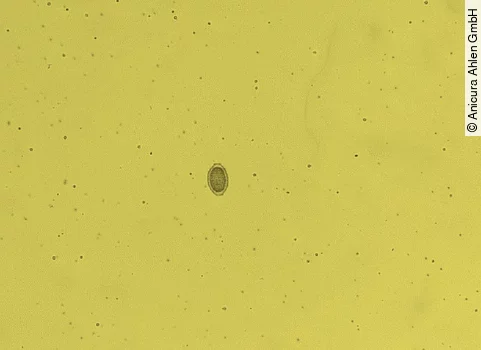

Als eine der einfachsten Untersuchungsmethoden folgt die Urinuntersuchung. Im Urinsediment können Eier des Parasiten nachgewiesen werden, sofern adulte Weibchen in der Niere vorhanden sind, was in bis zu 40% der Fälle vorkommt [15]. Die Eier von Dioctophyma renale messen 73-83μm in der Länge und 45-47μm in der Breite und sind damit verhältnismäßig groß im Vergleich zu anderen Nematodeneiern [4]. Charakteristisch ist die dicke Schale, die an den Längsseiten rau und an den Polen glatt und hell erscheint (Abb. 4 und 5). Damit gelingt eine gute Abgrenzung zu den Eiern von Capillaria plica, die als Begleitparasitose ebenfalls im Urin zu finden sein können (Abb. 6). Zusätzlich können im Urinsediment Entzündungsanzeichen wie Erythrozyten und Leukozyten vorhanden sein [11,15]. Aufgrund möglicher bakterieller Begleitinfektionen, sollte zudem eine bakteriologische Harnuntersuchung mit Antibiogramm erfolgen.